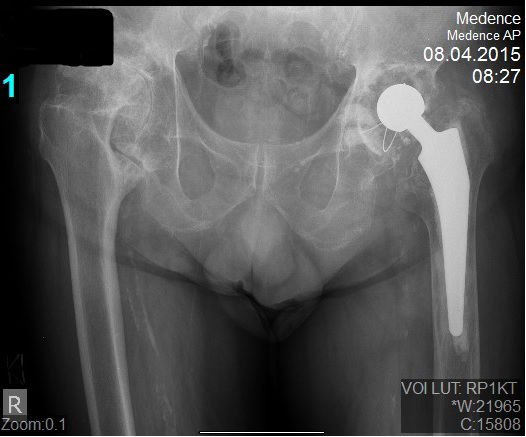

29 éves pályám során közel ezer térdprotézist és több mint kétezer csípőprotézist ültettem be. Az utóbbi években egyre több, nagy műszer igényű, összetett protézis revíziós műtétet végzek.

Fő érdeklődési köröm a biomechanika, műszerfejlesztés, új műtéti technikák kidolgozása és a nagyízületi endoprotetika.